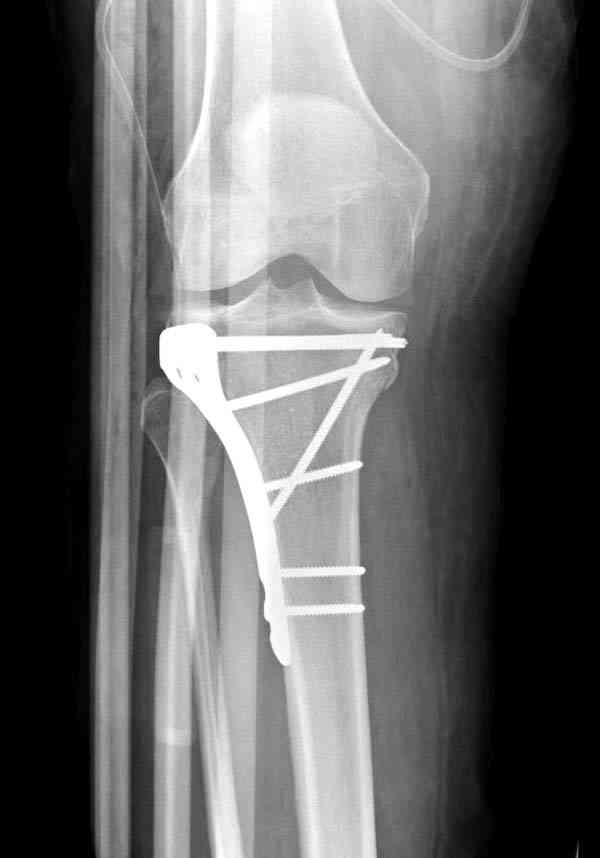

Нет, малоберцовый внизу, фиксацию проводим на верхнем эпифизе, где твердая кость. Задача состоит

в том, чтобы создать арматуру из нескольких проведенных шурупов на эпифизе.

Это техника применяется, когда имеется

центральная импрессия, а при ипрессии с краевым переломом - после приподнимания импрессии опорная (Butress) пластина, как на снимке.